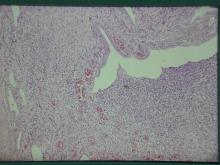

以上三個病例皆由超音波確診後,進行外科切除,手術取下之子宮外觀如下: 病例一:

子宮體及兩側子宮角膨大(圖1),子宮角切開可見腔內充滿血樣、膿樣分泌物,子宮內膜水腫,子宮內膜腺體囊腫性增生(圖2),子宮重量0.3 公斤。 病例二: